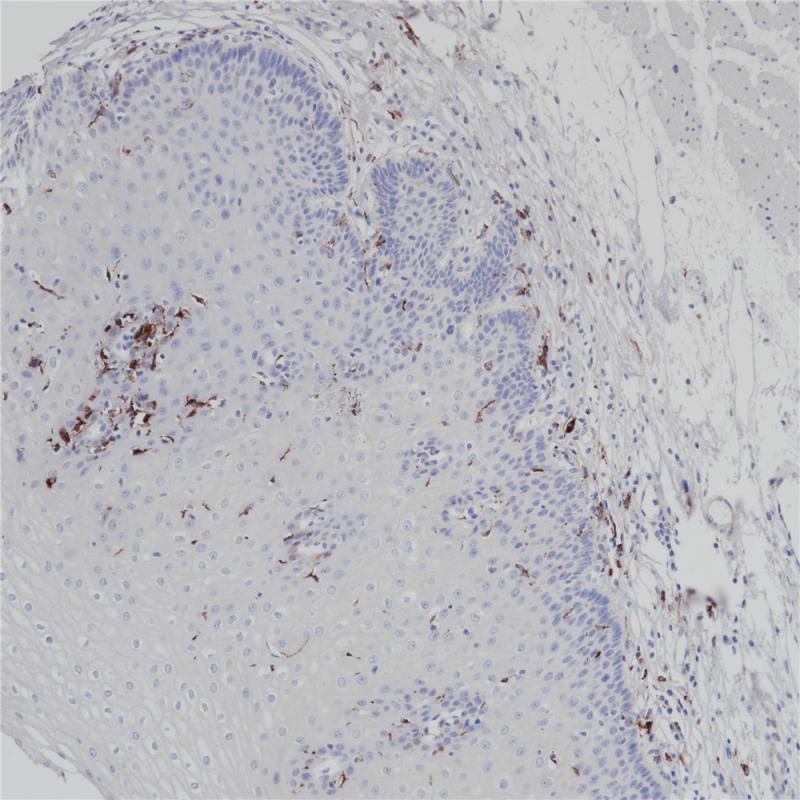

雌激素受体(ER)属于核受体超家族的类固醇受体,由553个氨基酸组成。雌激素受体分子具有三个结构域,即DNA结合中央结构域,C末端的激素结合结构域和N末端的转录激活结构域。ER参与女性性激素的调节功能,主要是17(E2),在一些目标组织的生长、分化和功能方面,如女性和男性生殖道,乳腺,骨骼和心血管系统。ER α存在于正常乳腺和子宫内膜组织的上皮细胞的细胞核,以及乳腺癌的亚型中。其次, ER α可作为一个肿瘤标志物,与抗孕酮受体的抗体组合,可用于腺癌的分类。

阳性对照

乳腺癌

亚细胞定位

细胞核